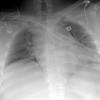

Nl Fat 2a

Date: 04/16/2005

Views: 4800